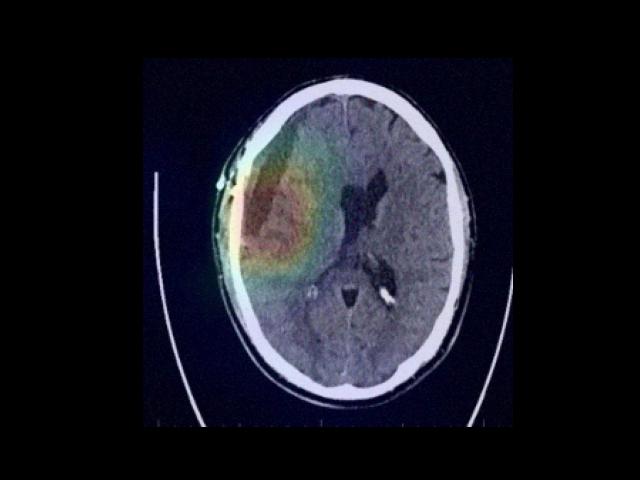

Sample Gallery